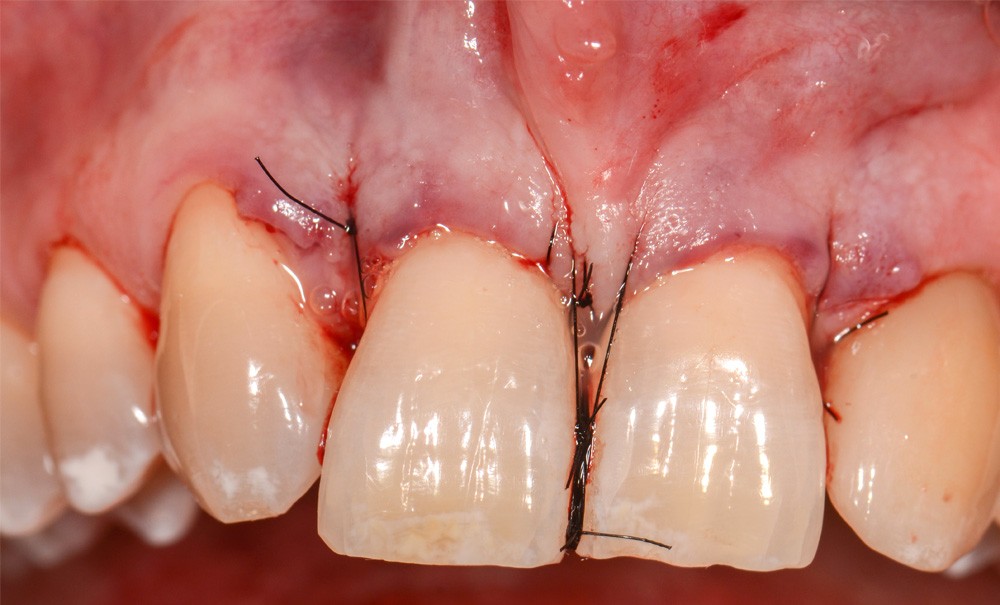

Synergie ortho-parodontale dans le traitement d’une lésion infra-osseuse associée à une migration dentaire secondaire

La parodontite de stade IV entraîne fréquemment le déplacement des dents antérieures maxillaires et elle est souvent associée à des défauts infra-osseux. Ces lésions, après thérapeutique parodontale non chirurgicale, sont traitées par des procédures de régénération chirurgicale. Après obtention d’un parodonte sain réduit avec antécédent de parodontite, il est d’usage d’instaurer un traitement orthodontique de réalignement des arcades dentaires [1]. La combinaison de ces deux protocoles a montré une nette amélioration des résultats cliniques et radiographiques. Il a été démontré que le traitement orthodontique doit toujours être réalisé après la chirurgie de régénération, mais l’intervalle entre ces deux procédures est discuté. Le cas clinique présenté montre les résultats obtenus à deux ans après traitement orthodontique mis en place dans le mois qui a suivi la chirurgie parodontale de régénération d’une lésion intra-osseuse.